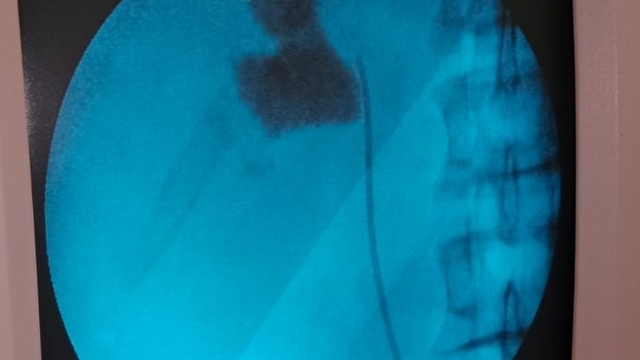

Kırşehir'de bir hastanın böbreğindeki 6 santimetrelik taş, kapalı ameliyatla alındı.

Kırşehir Eğitim ve Araştırma Hastanesinden yapılan yazılı açıklamaya göre, hastaneye başvuran İlhan Çakır'ın kontrollerinde böbreğinde 6 santimetrelik taş tespit edildi.

Üroloji Kliniğinden Uzm. Dr. Talip Göktaş ve ekibi tarafından kapalı ameliyatla hastanın böbreğindeki taş başarılı bir şekilde çıkarıldı.

Uzm. Dr. Talip Göktaş da kontrollerde hastanın sol böbreğinde 6 santimlik taş tespit ettiklerini, kapalı böbrek taşı yöntemi PNL ile ameliyatı gerçekleştirdiklerini belirterek, "Hastamız 1 gün sonra taburcu edildi. Bu yöntemle hastalarımız açık ameliyatlara göre erken dönemde işlerine dönebiliyor ve daha konforlu bir şekilde ameliyat sürecini atlatabiliyor. 5 yıl içinde hastanemizde 50'den fazla bu tarz ameliyatları başarıyla gerçekleştirdik." ifadesini kullandı.